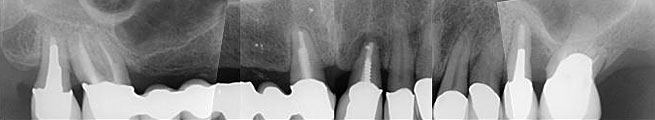

Abb. 1a: Röntgenstatus vom 14. Juli 2009

Abb. 1b: Röntgenstatus vom 14. Juli 2009

Abbildung 1: Radiologisch liegen folgende Diagnosen vor: Insuffiziente Wurzelfüllungen an 18,17,21,26, Beherdung an 21, zervikale Karies an 17,11, enge Wurzelproximität an 18,17, Tiefer intraalveolärer Knochendefekt an 25,26.